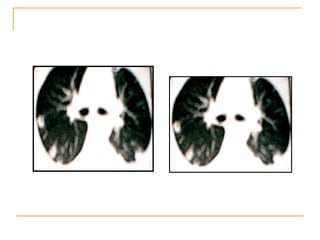

Neumonía por  P. Carinii  en paciente VIH

Paciente VIH positivo con neumonía por  Pneumocytis carinii  (fase subaguda o en resolución)

Neumonía por  Pneumocystitis carinii.  Patrón pulmonar intersticial bilateral.